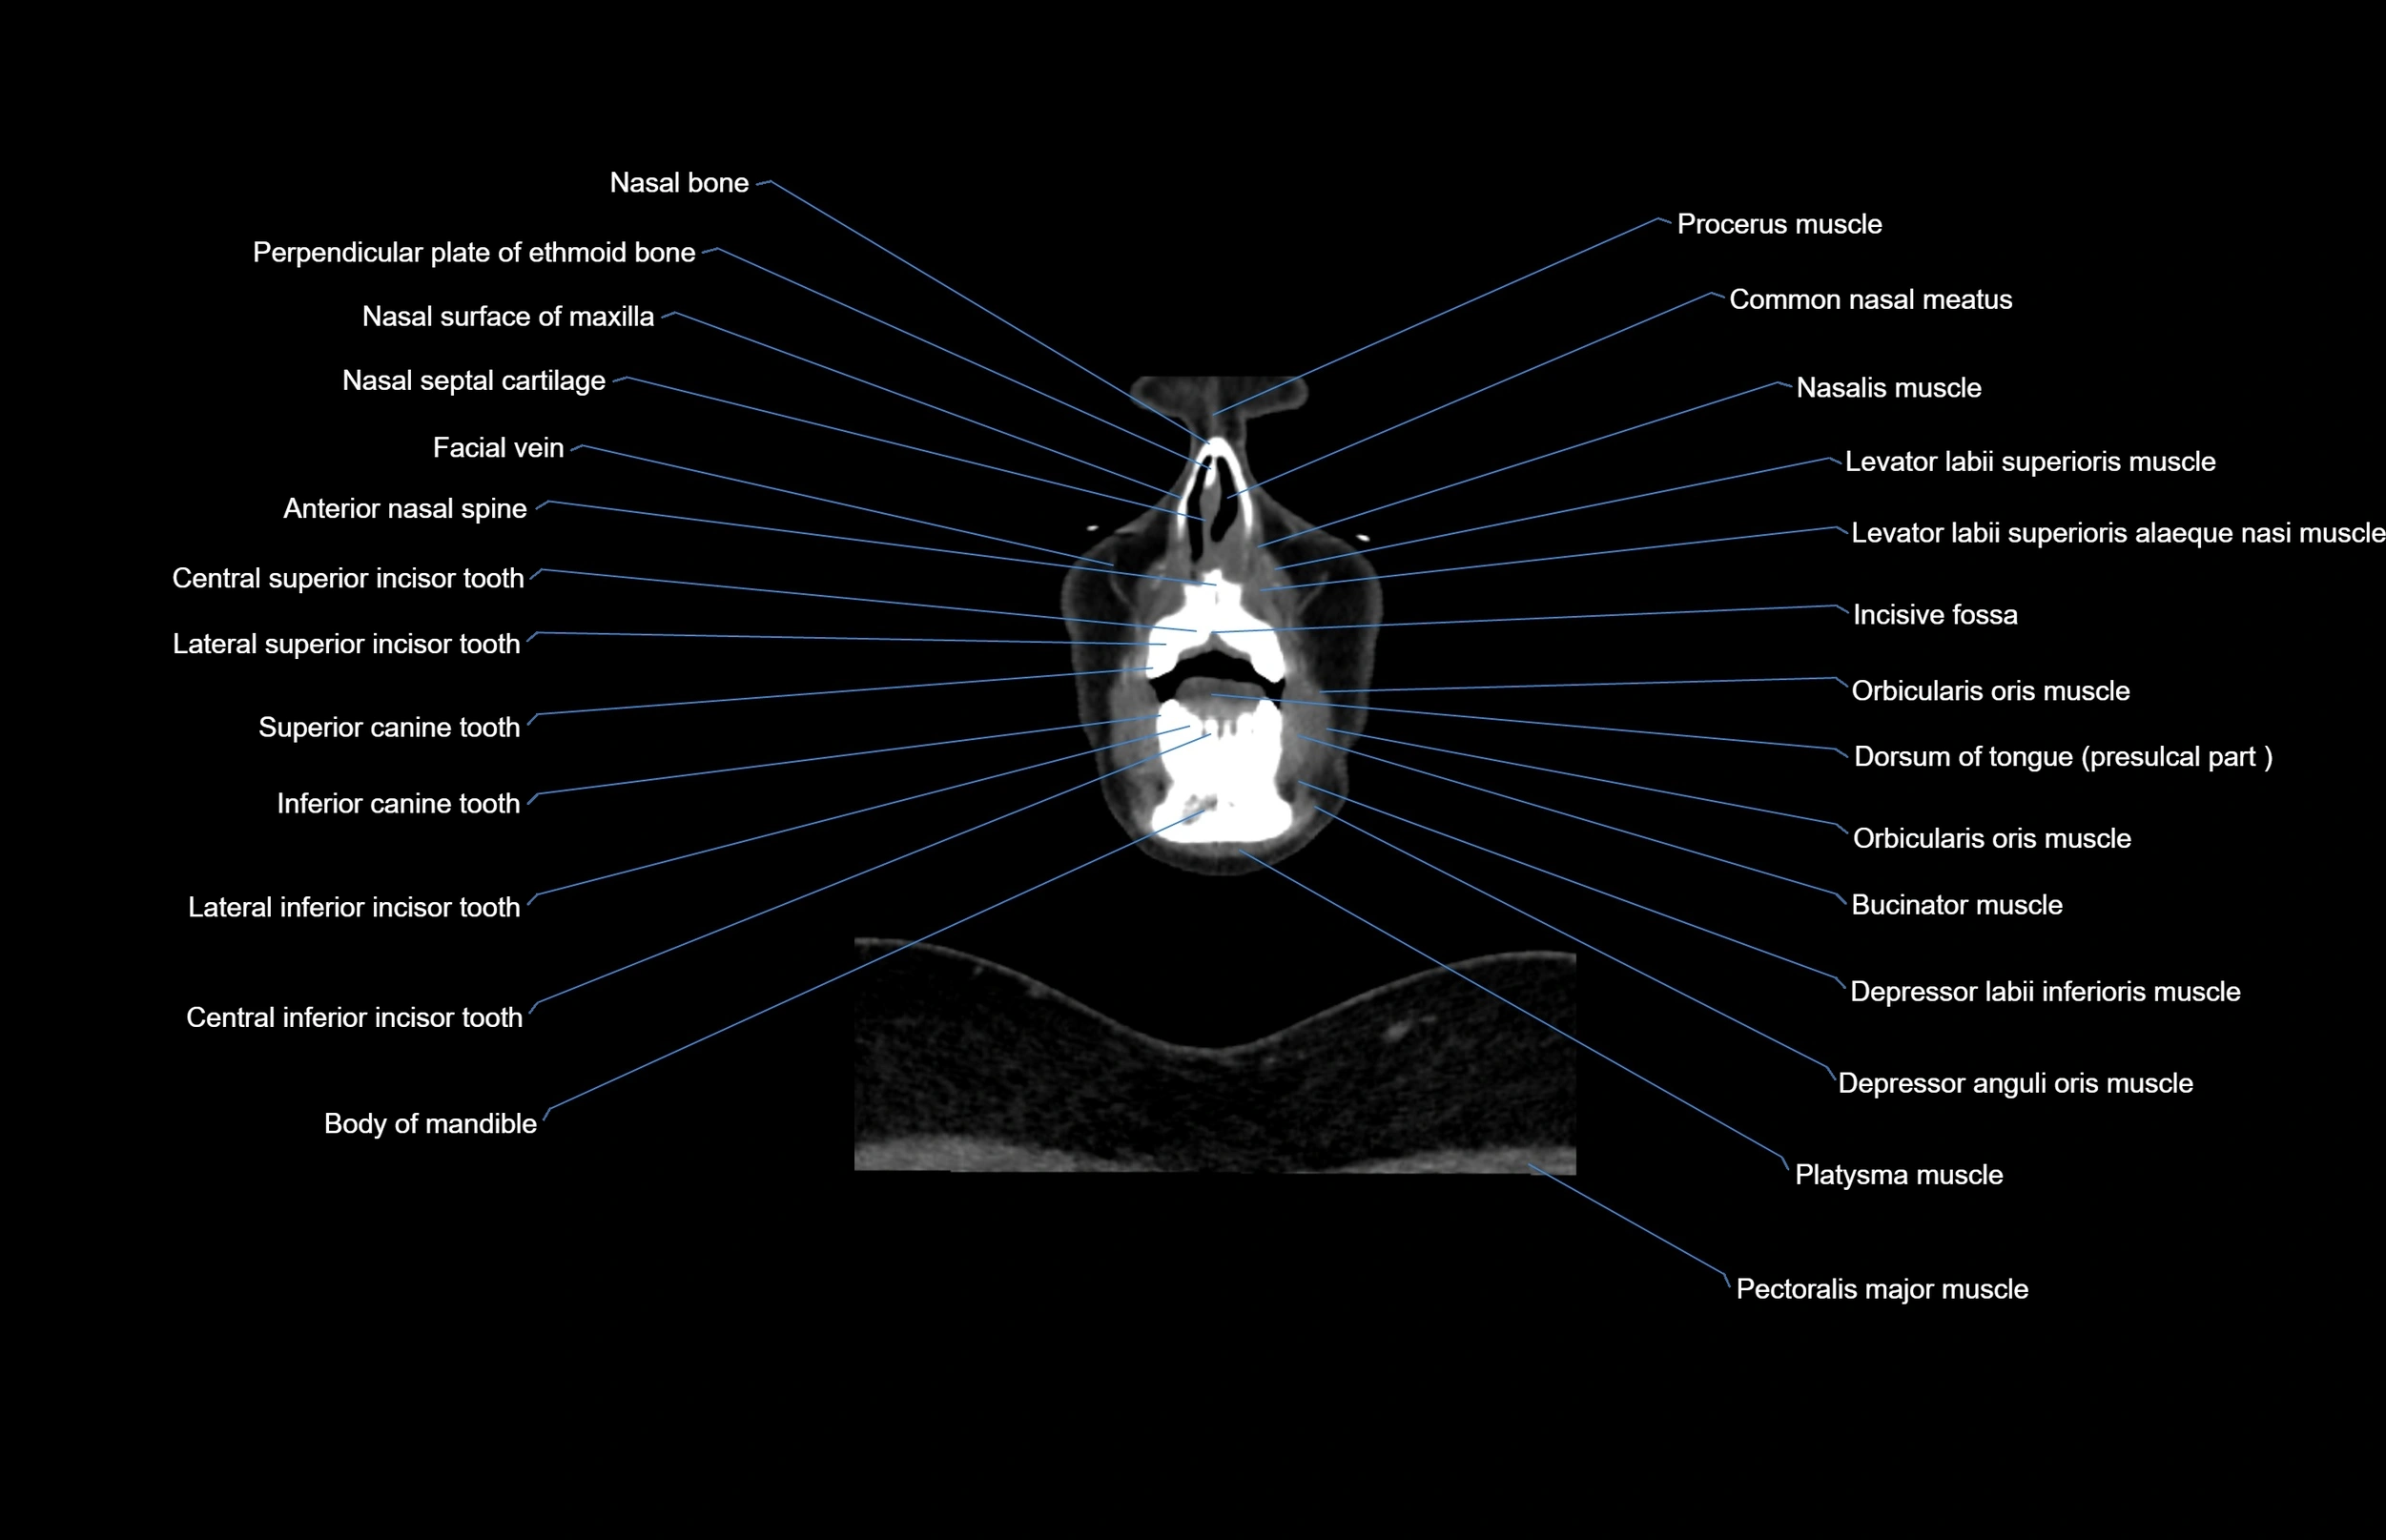

- Anterior nasal spine

- Body of mandible

- Buccinator muscle

- Central superior incisor tooth

- Common nasal meatus

- Depressor anguli oris muscle

- Depressor labii inferioris muscle

- Dorsum of tongue

- Facial vein

- Genioglossus muscle

- Inferior canine tooth

- Lateral inferior incisor tooth

- Lateral superior incisor tooth

- Levator labii superioris alaeque nasi muscle

- Levator labii superioris muscle

- Nasalis muscle

- Orbicularis oris muscle

- Pectoralis major muscle

- Platysma muscle

- Risorius muscle